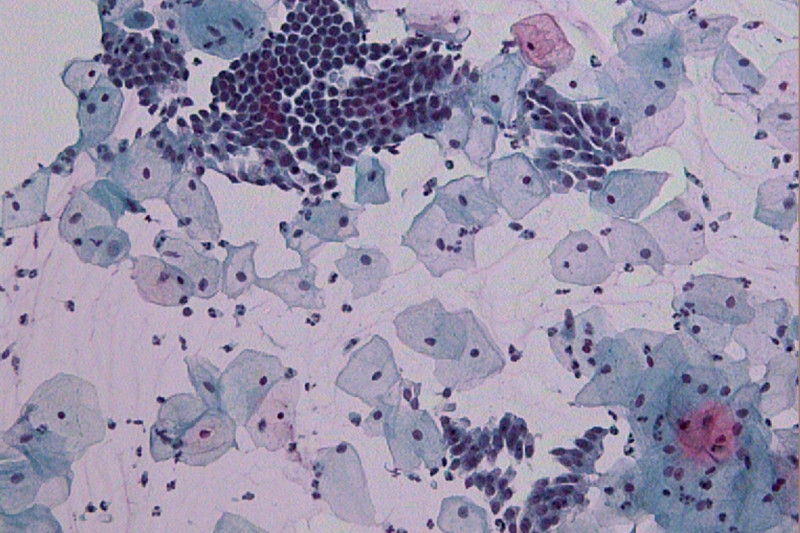

Imagem de Citologia Oncótica

O exame de citologia oncótica refere-se ao preventivo do colo do útero, o papanicolau, e serve para o rastreamento precoce do câncer de colo de útero e doenças sexualmente transmissíveis.

Os resultados da citologia do colo do útero são fornecidos pelo médico patologista, após a avaliação das células recolhidas no exame ginecológico.